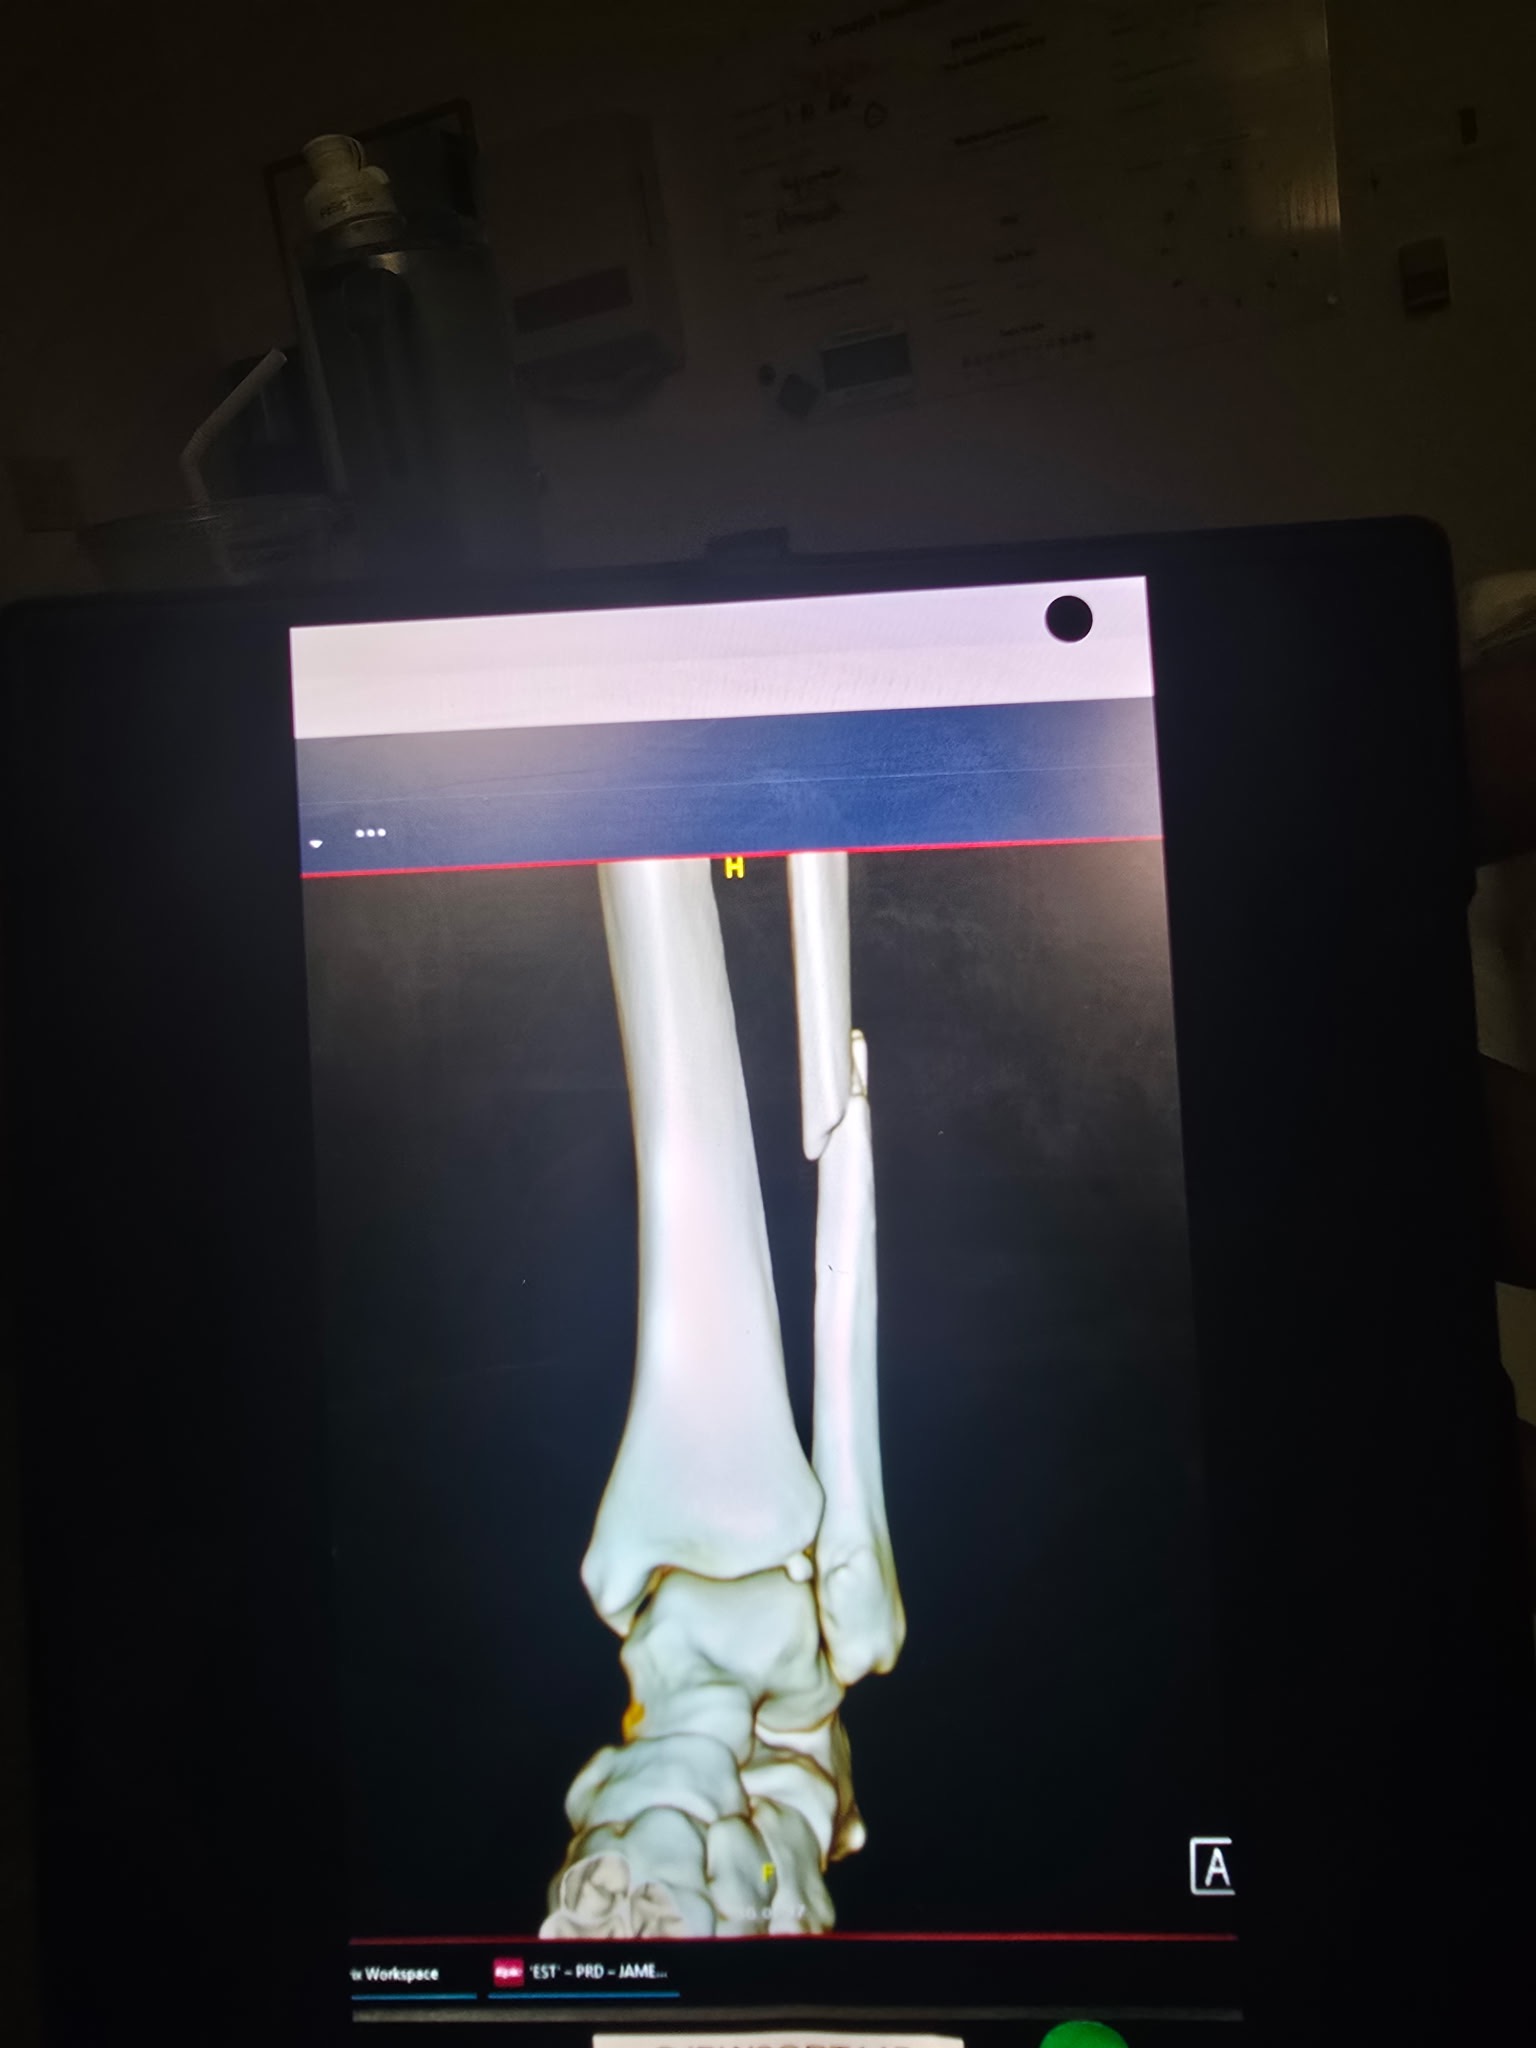

On 01/10/2026, Chelsea slipped and fell on the ice in her driveway, causing a dislocated ankle along with fractures to her ankle and leg. She went to the ER the same day, where the dislocation was stabilized, and she was admitted to the hospital. On 01/11/2026, she underwent her first surgery, where a rod, plate, and screws were placed to stabilize her injuries.

At her follow-up appointment with her orthopedic surgeon on 01/14/2026, it was determined that there had been too much swelling during the first surgery, and she would need a second surgery to place an additional plate on the back of her ankle. That second surgery was completed on 01/15/2026.